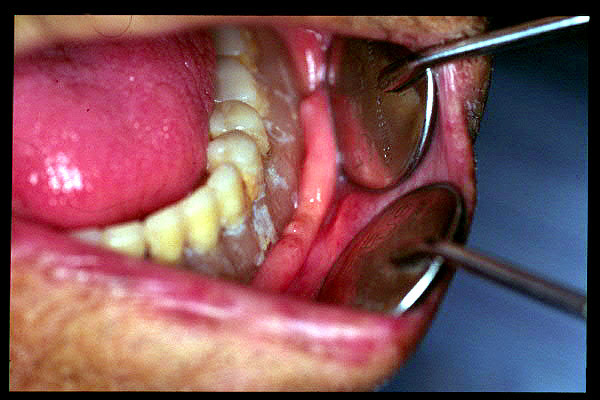

CM Enfermedad periodontal avanzada. Cálculos.